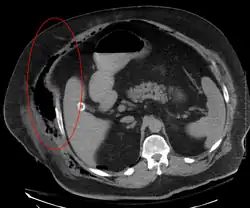

Czujność należy również zachować przy ocenie wyników badań obrazowych. Zdjęcie RTG nie potrafi uwidocznić zmian zachodzących w głębi tkanek. Tomografia komputerowa (bez kontrastu) i MRI są standardami pozwalającymi rozpoznać zakażenie w większości wypadków. USG może ułatwić stwierdzenie przestrzeni płynowych, dostępnych do nakłucia igłą aspiracyjną. Jako niezależne narzędzie diagnostyczne nie przedstawia jednak większej wartości.